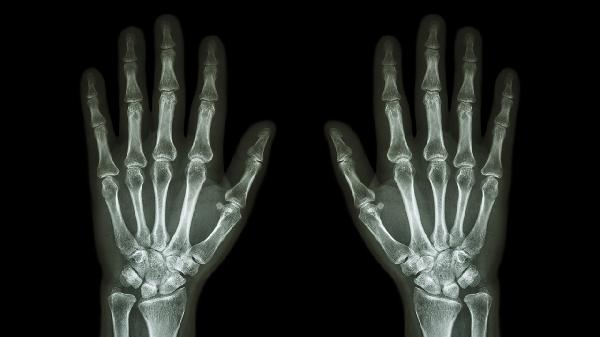

手指关节腱鞘炎是怎么引起的

手指关节腱鞘炎可能由过度使用手指、外伤、感染、风湿性疾病、退行性变等原因引起,可通过休息制动、药物治疗、物理治疗、封闭注射、手术松解等方式治疗。